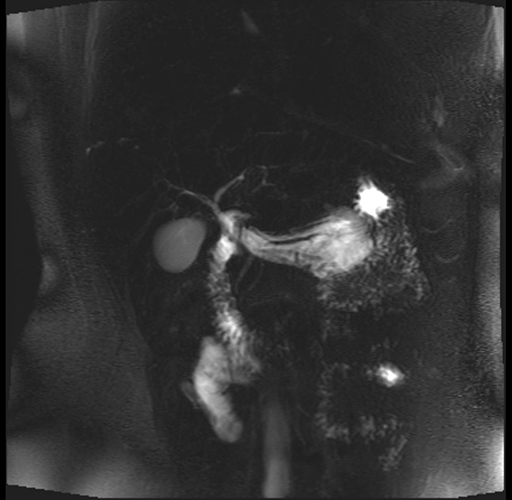

Imaging Analysis

Look through the patient's CT scan to identify any areas of concern for the necessary procedure.

Based on your CT findings, which issue(s) are present and would give reason for "planned slowing down moment(s)" in this case?

Considering a standard distal pancreatectomy procedure, what step(s) of the operation would you do differently in this case?